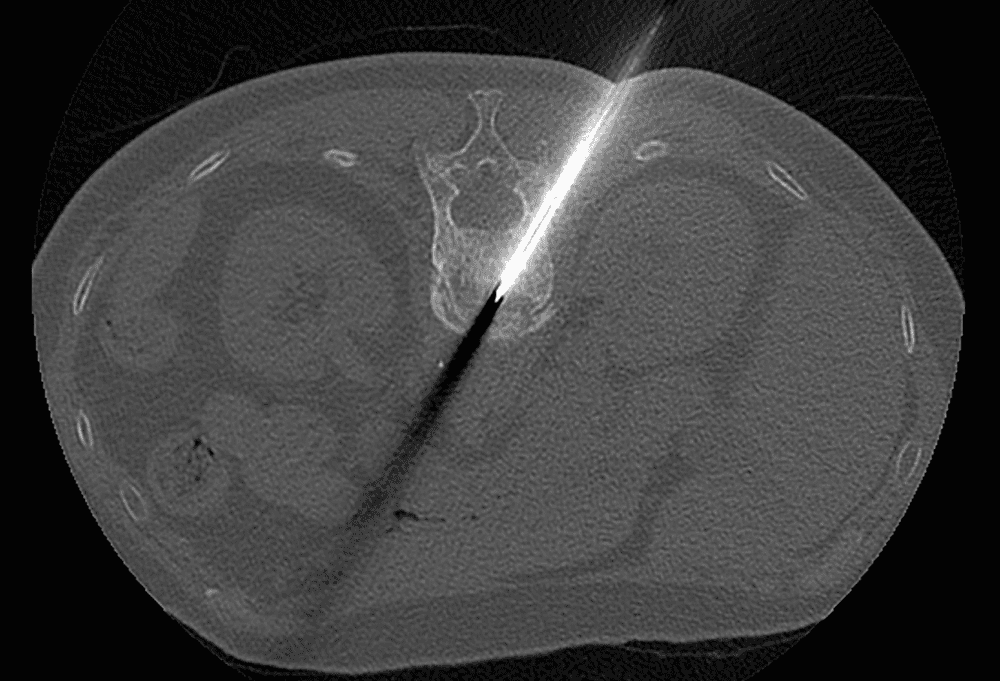

L'implant SPINEJACK vise à réduire la fracture in situ par restauration de la hauteur anatomique du corps vertébral.

Technique de traitement des fractures vertébrales ostéoporotiques